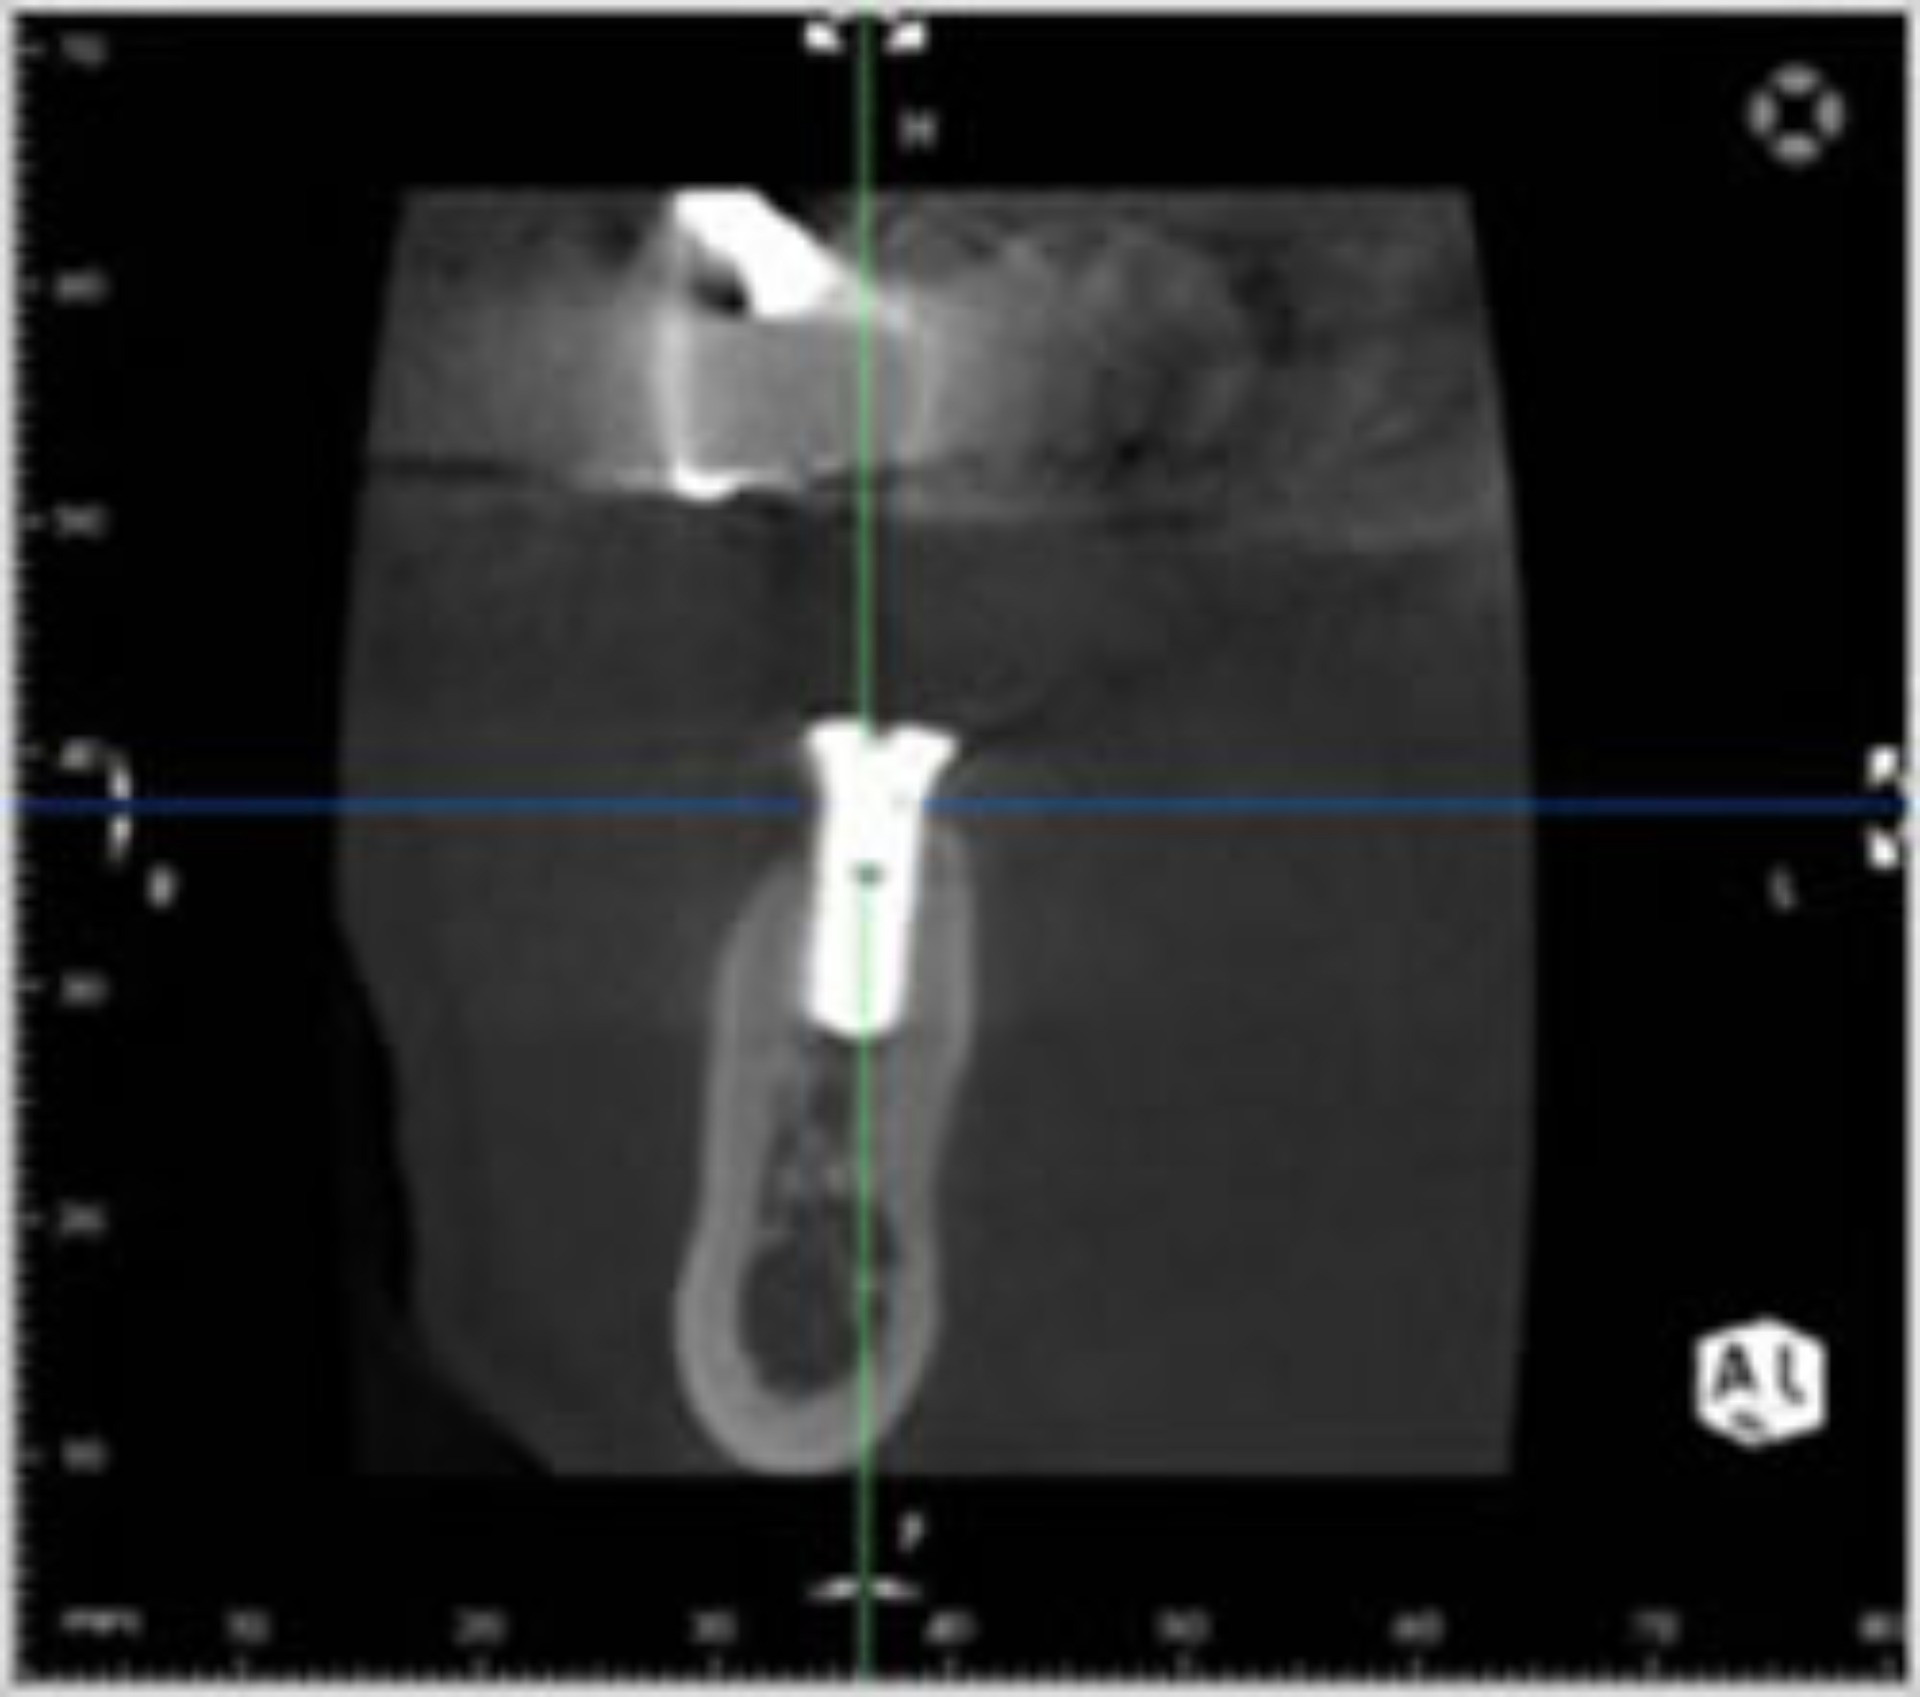

精度の高い診断・治療を行うために、最新鋭歯科用CTを導入しました。

CTとは、コンピューターを駆使したデータ処理と画像の再構成で、断層写真を得ることができる装置です。

従来のレントゲン画像は平面像(二次元)でしたが、歯科用CT画像は立体画像(三次元)で表現することが可能ですので、歯周病の現状や歯の根の形態、歯の周りの骨の状態など、お口の中をより細部まで、正確に診断することができます。画像は、歯科用ユニットに備え付けられたモニターに映し出し、ご確認いただけます。

また、歯科用CTは、医科用のCTとは異なり、歯科用にカスタマイズされたもので、放射線量は医科用CT の10分の1以下で被爆量が非常に少なくなっています。超高解像度画像から広範囲撮影まで可能で、医科用CTの約5倍の情報量を得ることができます。

CT画像からは、従来のレントゲンでは見えなかった顎の骨の立体的な形態や、神経の位置把握、さらに骨密度の診査にも利用できます。 |

インプラント治療の成功のカギとなる骨の量・骨の密度がCTにより正確に算出されることで治療の成功率は飛躍的に向上します。

インプラント治療の成功のカギとなる骨の量・骨の密度がCTにより正確に算出されることで治療の成功率は飛躍的に向上します。

またインプラントの埋入量や方向なども的確にシミュレートされるので、CT撮影なしで行う手術に比べ安全性も格段に向上します。

骨が溶けてしまう病気である歯周病の検査では、これまでプローブという器具で骨のない場所を手探りで見つけていました。

骨が溶けてしまう病気である歯周病の検査では、これまでプローブという器具で骨のない場所を手探りで見つけていました。

CT撮影では三次元的に骨のない場所が画面上で一目で分かるためプローブの入らない場所でも正確に病巣を見つけることができます。

根の本数や神経の入っている管の方向、そして位置を正確に把握することができます。

また、細かい根の破折も発見できるので、早期治療が可能になります。

CT画像では、埋まった歯や周囲の歯、神経や血管の位置関係を容易に確認することができます。